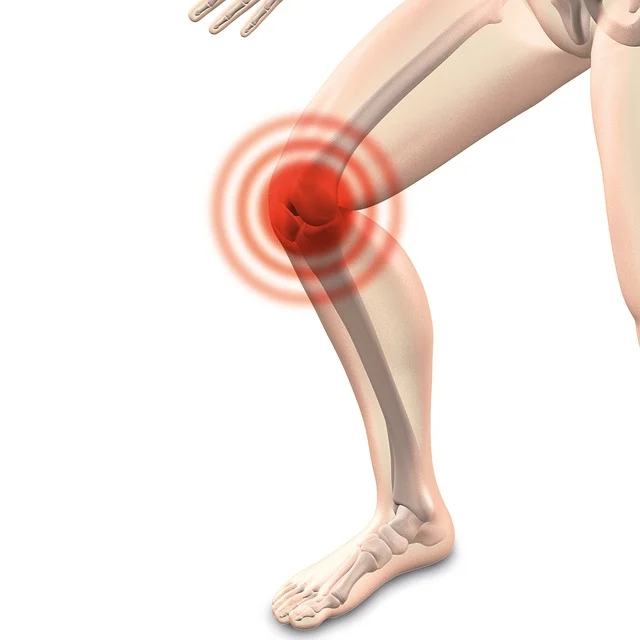

관절은 우리 몸을 움직이게 해주는 핵심 기관으로, 연골, 활액, 인대 등의 복합적인 구조로 이루어져 있습니다. 하지만 나이가 들거나 과도한 활동, 부상 등으로 인해 관절이 손상되면 통증과 불편함이 생길 수 있습니다. 이런 경우 관절 영양제가 도움이 될 수 있습니다.

관절 영양제는 관절 건강에 필요한 주요 영양소를 공급하여 연골 재생과 윤활 기능을 개선하고, 염증을 줄여 통증을 완화시키는 것으로 알려져 있습니다. 하지만 모든 관절 영양제가 동일한 효과를 보이는 것은 아니므로, 성분과 효능을 꼼꼼히 살펴볼 필요가 있습니다.

무릎 관절

- 콘드로이틴: 연골 재생과 관절 기능 개선

- MSM: 관절 염증 감소와 통증 완화